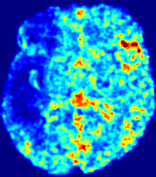

LesionRefer to captionRefer to captionRefer to captionRefer to captionRefer to captionRefer to caption𝐕rgbsubscript𝐕𝑟𝑔𝑏{\bf{V}}_{rgb}Refer to captionRefer to captionRefer to captionRefer to captionRefer to captionRefer to caption𝐕2subscriptnorm𝐕2{\|\bf{V}}\|_{2}Refer to captionRefer to captionRefer to captionRefer to captionRefer to captionRefer to captionRefer to caption3.53.53.52.82.82.82.12.12.11.41.41.40.70.70.70.00.00.0(mm/s)𝑚𝑚𝑠(mm/s)D𝐷DRefer to captionRefer to captionRefer to captionRefer to captionRefer to captionRefer to captionRefer to caption0.0200.0200.0200.0160.0160.0160.0120.0120.0120.0080.0080.0080.0040.0040.0040.0000.0000.000(mm2/s)𝑚superscript𝑚2𝑠(mm^{2}/s)Slice #1Slice #2Slice #3Slice #4Slice #5Slice #6

Figure 3: PIANO feature maps for one stroke patient, where the lesion is located in the left hemisphere. Top row: segmented stroke lesion region (white) on different slices, obtained from ISLES 2017. The corresponding slices for the PIANO feature maps are shown in the following rows.

For a better insight into an estimated velocity field 𝐕𝐕{\bf{V}} and diffusion field 𝐃𝐃{\bf{D}}, we compute the following maps: (1) 𝐕rgbsubscript𝐕𝑟𝑔𝑏{\bf{V}}_{rgb}: Color-coded orientation map of 𝐕=(Vx,Vy,Vz)T𝐕superscriptsuperscript𝑉𝑥superscript𝑉𝑦superscript𝑉𝑧𝑇{\bf{V}}=(V^{x},V^{y},V^{z})^{T}, obtained by normalizing 𝐕𝐕{\bf{V}} to unit length and mapping its 3 components to red, green, blue respectively; (2) 𝐕2subscriptnorm𝐕2\|{\bf{V}}\|_{2}: 222 norm of 𝐕𝐕{\bf{V}}; (3) D𝐷D: scalar field in Eq. 5.

Fig. 3 and Fig. 4 show the PIANO feature maps estimated from two ISLES 2017 patients: all are highly consistent with the lesion in both cases. Details of the blood flow trajectories are revealed in 𝐕rgbsubscript𝐕𝑟𝑔𝑏{\bf{V}}_{rgb} by the ridged patterns and the sharp changes of colors in the unaffected (right) hemisphere, while the flat patterns appearing within the lesion provide little directional information about the velocity and indicate low velocity magnitudes. Velocity magnitudes are more directly visualized via 𝐕2subscriptnorm𝐕2\|{\bf{V}}\|_{2}, from which one can easily locate the lesion where 𝐕2subscriptnorm𝐕2\|{\bf{V}}\|_{2} is low. D𝐷D also indicates lower diffusion values in the lesion, though with less contrast potentially due to the fact that it captures the accumulated effect of CA diffusion at the voxel-level.